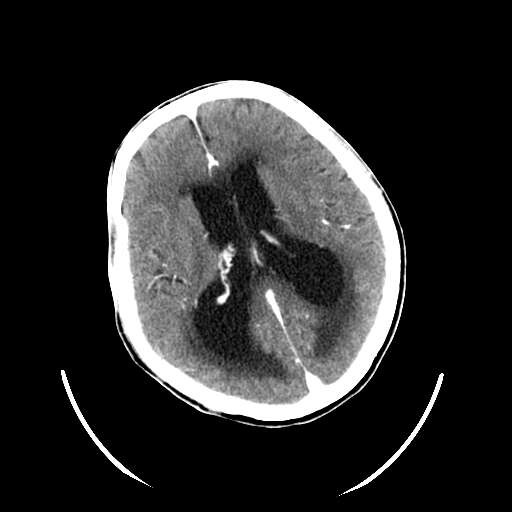

以下是引用hhcckk在2007-10-9 10:03:00的发言:[br]galen';s静脉瘤又称大脑大静脉瘤,是由于动静脉短路,大量血流进入galen';s静脉(大脑大静脉),造成该静脉瘤样扩张所致,病理上典型的galen';s静脉瘤包括一明显扩张的囊状galen';s静脉和引流galen';s静脉的短路血管,,这些短路血管多来源于颈内动脉系统或基底动脉系统,多异常扩大、迂曲。巨大的galen';s静脉瘤可造成中脑压迫,导水管闭塞,引起梗阻性脑积水。[br]galen';s静脉瘤ct表现较典型,根据其部位、形态、增强前后表现及脑积水表现较易诊断。[br]支持张主任,此病人病灶强化明显,正常松果体增强后在病灶的后方可见,可以再做个mr,血管性的病灶在mr上有流空效应,增强后明显强化,诊断更有把握